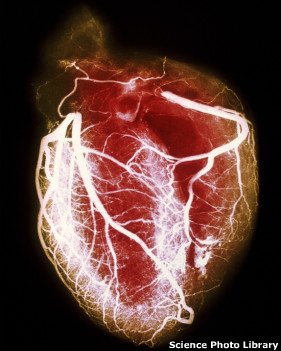

آنژیوگرافی مهمترین راه تشخیص انسداد عروق کرونر است